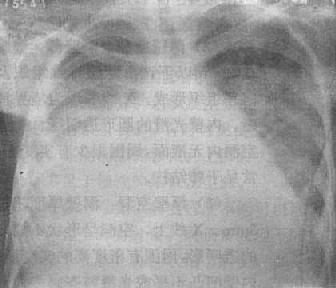

1.渗出与实变 机体的急性炎症反应主要表现是渗出(exudation)。渗出性病变的范围不同,在X线上表现为密度不太高的较为均匀的云絮状影,边缘模糊,与正常肺间无清楚界限(图3-1-10)。肺部急性炎症进展至某一阶段,肺泡内气体即被由血管渗出的液体、蛋白及细胞所代替,形成渗出性实变(consolidation)。渗出是产生实变常见原因之一。实变在大体病理上为肺泡内的空气被病理性液体或组织所代替。这些病理液体可以是炎性渗出液、血液及水肿液。见于肺炎、渗出性结核、肺出血及肺水肿等。由于病理性液体可以通过肺泡孔向邻近肺泡蔓延。因而病变区与正常肺组织间无截然分界,而呈逐渐称行状态。实变可大可小,多数连续的肺泡发生实变,则形成单一的片状致密影,边缘模糊,密度较均匀。多处不连续的实变,隔以含气的肺组织,则形成多数小片状致密影,边界模糊。小范围的实变随病变的进展可成为大片实变。如实变占据整个肺叶,其边界至叶间胸膜,则形成边缘锐利以叶间胸膜为界的全叶性实变(图3-1-11)。实变中心区密度较高,边缘区较淡。以浆液渗出或水肿为主的实变密度较低;以脓性渗出为主的实变密度较高;以纤维素渗出为主的实变密度最高。当实变扩展至肺门附近,则较大的含气支气管与实变的肺组织常形成对比,而在实变的影像中可见到含气支气管分支影,称支气管气像(air bronchogram)。

图3-1-10 渗出性病变

两肺浸润型肺结核,两肺第1~2前肋间出现边

缘模糊、密度不太高的云絮状影

图3-1-11 肺实变(右中叶大叶性肺炎)

相当于右肺中叶密度均匀增高,后前位上,上缘清楚,下缘模糊,

侧位上呈三角形致密影,尖端在肺门区